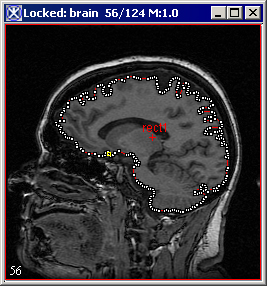

Figure 3. An initial VOI (A) and VOI after applying the Evolve Boundary > Active Contour algorithm with the default parameters (B)

A

B